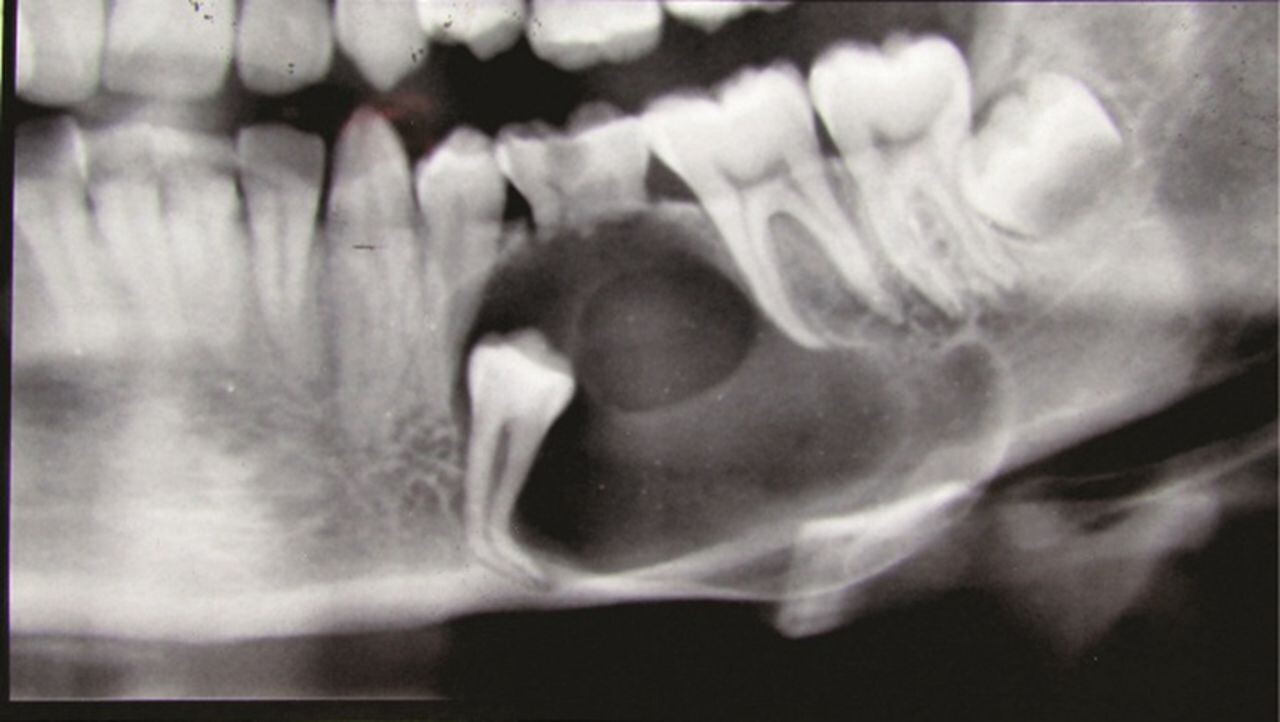

Formation of Cysts or Tumours

If the wisdom teeth problems are not dealt in an appropriate manner, the tooth will develop a sac within the jawbone. This sac has the ability to fill with fluid, which gradually develops into the formation of cyst, damaging the teeth, jawbone, and nerves. There are chances that this cyst could progressively develop into a tumour if untreated which could ultimately result in the removal of tissue and jaw bones.

You can’t prevent the occurrence of an impacted wisdom tooth, but with a regular dental check-up, your dentist will help you monitor the emergence of the wisdom tooth, with the help of dental X-rays and advanced methodologies, which might indicate the need of wisdom teeth removal.